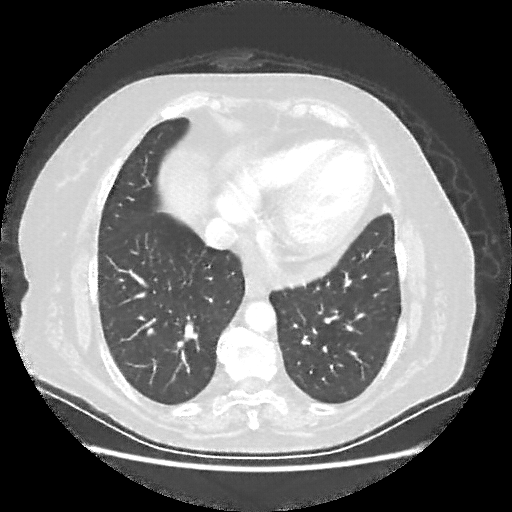

Original VENOUS CT scan

No window - Raw intensity values

Lung window (WL -600, WW 1500 β†’ Low βˆ’1350, High +150)